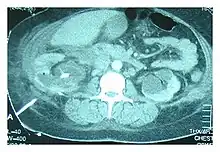

Abdominal ultrasonography and CT scan can help diagnose the underlying condition of the genitourinary tract. If other methods prove inconclusive, an accurate diagnosis can be made by a technetium-99m kidney scan, which shows albumin labeled with 99Tc that translocates into the pleural space from the genitourinary tract.[4]